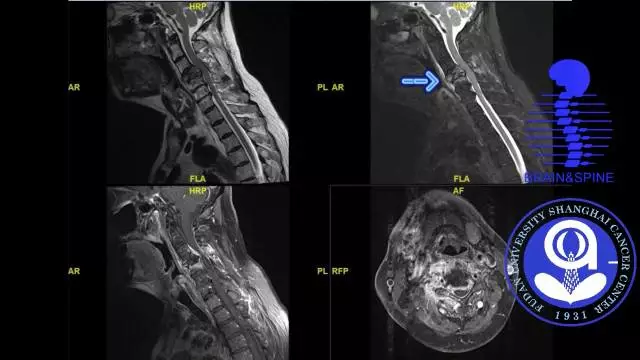

手术过程